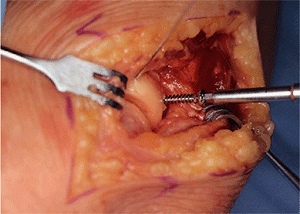

![]() |

|

Figure 5-8. A,B:

The forearm is slightly pronated, exposing the posterior half of the fracture fragment. A drill sleeve is used and a 2.0-mm drill bit is employed. |

Figure 5-9.

A 2.7-mm drill bit is then used to overdrill the fracture fragment to receive the 2.7-mm screw. Care should be taken not to split small slice fracture fragments with the overdrilling process. |